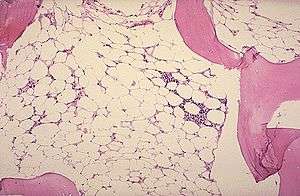

Micrograph of bone marrow taken from a patient with aplastic anemia | |

The definitive diagnosis is by bone marrow biopsy; normal bone marrow has 30–70% blood stem cells, but in aplastic anemia, these cells are mostly gone and replaced by fat.[2][3]